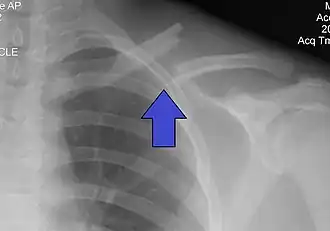

Перелом ключицы — патологическое состояние, проявляющееся нарушением анатомической целостности ключицы. Чаще всего переломы происходят в средней трети на границе наружной и средней третей ключицы, на наиболее изогнутой и истончённой её части. Наиболее часто встречающиеся — косые и оскольчатые.

Переломы средней трети ключицы распространенная травма, составляющая от 2 до 5% всех переломов, от 35 до 45% повреждений верхних конечностей. Согласно результатам различных биомеханических исследований, средняя треть —наиболее слабое место ключицы, с чем связана высокая частота переломов этой локализации[1].

Локальная болезненность, припухлость, деформация, кровоизлияние и укорочение надплечья, плечо опущено и смещено кпереди. Периферический отломок вместе с верхней конечностью под влиянием её тяжести и сокращения большой грудной и подключичной мышцы смещается вниз, вперёд и внутрь. Центральный отломок под воздействием грудино-ключичной мышцы смещается кверху и сзади. Отломки сближаются и заходят один на другой.

Выполняется рентген в прямой и боковой проекциях.